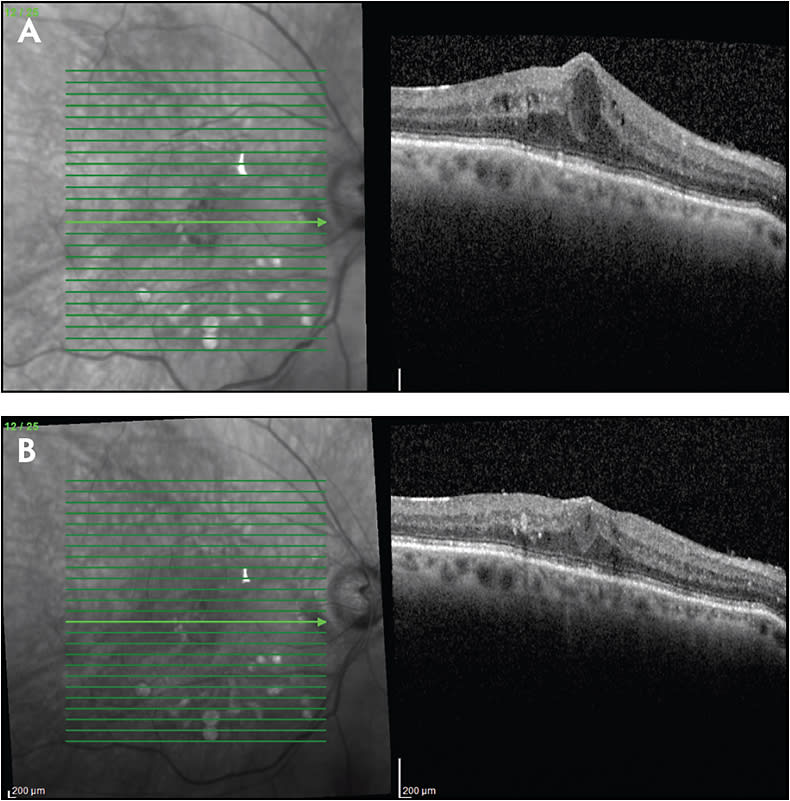

Currently available corticosteroids include the dexamethasone delivery system (Ozurdex; Allergan), the fluocinolone acetonide insert (Iluvien; Alimera), and off-label triamcinolone acetonide. When initiating corticosteroid therapy, the preferred options are the dexamethasone delivery system (which is FDA approved for DME) or intravitreal triamcinolone (which is used off label for DME) due to their relatively short durations of action (approximately 3 months) (Figure 3). Triamcinolone is less expensive, somewhat easier to inject, and may be associated with less patient discomfort than the dexamethasone delivery system, which comes packaged in a proprietary injector with a larger needle (22 gauge) than is generally used to inject intravitreal triamcinolone.